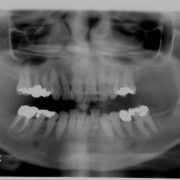

Alveolar Cleft (Defect in the Upper Jaw) Repaired with a Hip Bone Graft

After Bone Graft